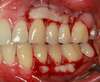

CAS GENCIVE  n°1

GREFFE GINGIVALE  ESTHETIQUE sur 2 INCISIVES du bas

intérêt santé + confort + esthétique